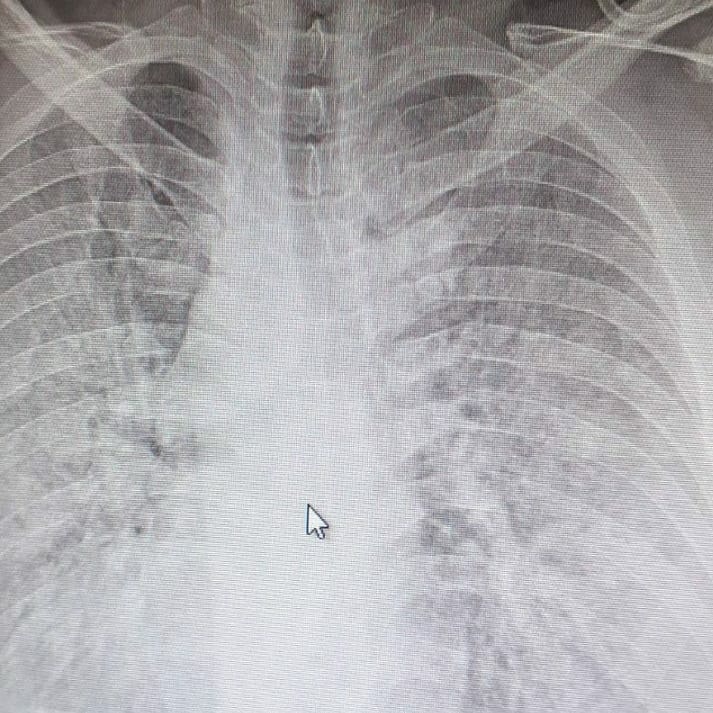

Tutje ai ka publikuar një rentgen të mushkërive ku shihet se si koronavirus i ka sulmuar ato, transmeton Gazeta Metro.

”Shikoni një rentgen të mushkërive si është katandisur nga ky virus. Ky rentgen nuk është i një plaku 90 vjeçar, por i një të riu nën moshën 30 vjeçar që më herët nuk ka pasur kurrfarë sëmundje shoqëruese”, ka shkruar ai.

Më poshtë keni rentgenin e publikuar nga doktori Bytyqi si dhe një rentgen që tregon se si duhet të jenë në gjendje normale mushkëritë.